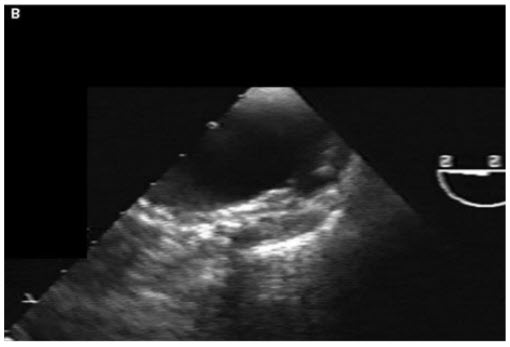

Despite severe atheroma in the aorta, the physician taking care of the patient is not convinced that he does not have an acute coronary syndrome and performs a cardiac catheterization. It shows that the grafts are patent and there is no culprit lesion in the native vessels. He then decides to perform aortography and a focal outpouching is seen in the aortic wall in the distal ascending aorta (Fig. below).

Contrast dye collects slowly in this region. The patient’s chest pain is intensifying. A TEE is also performed (Fig. below).